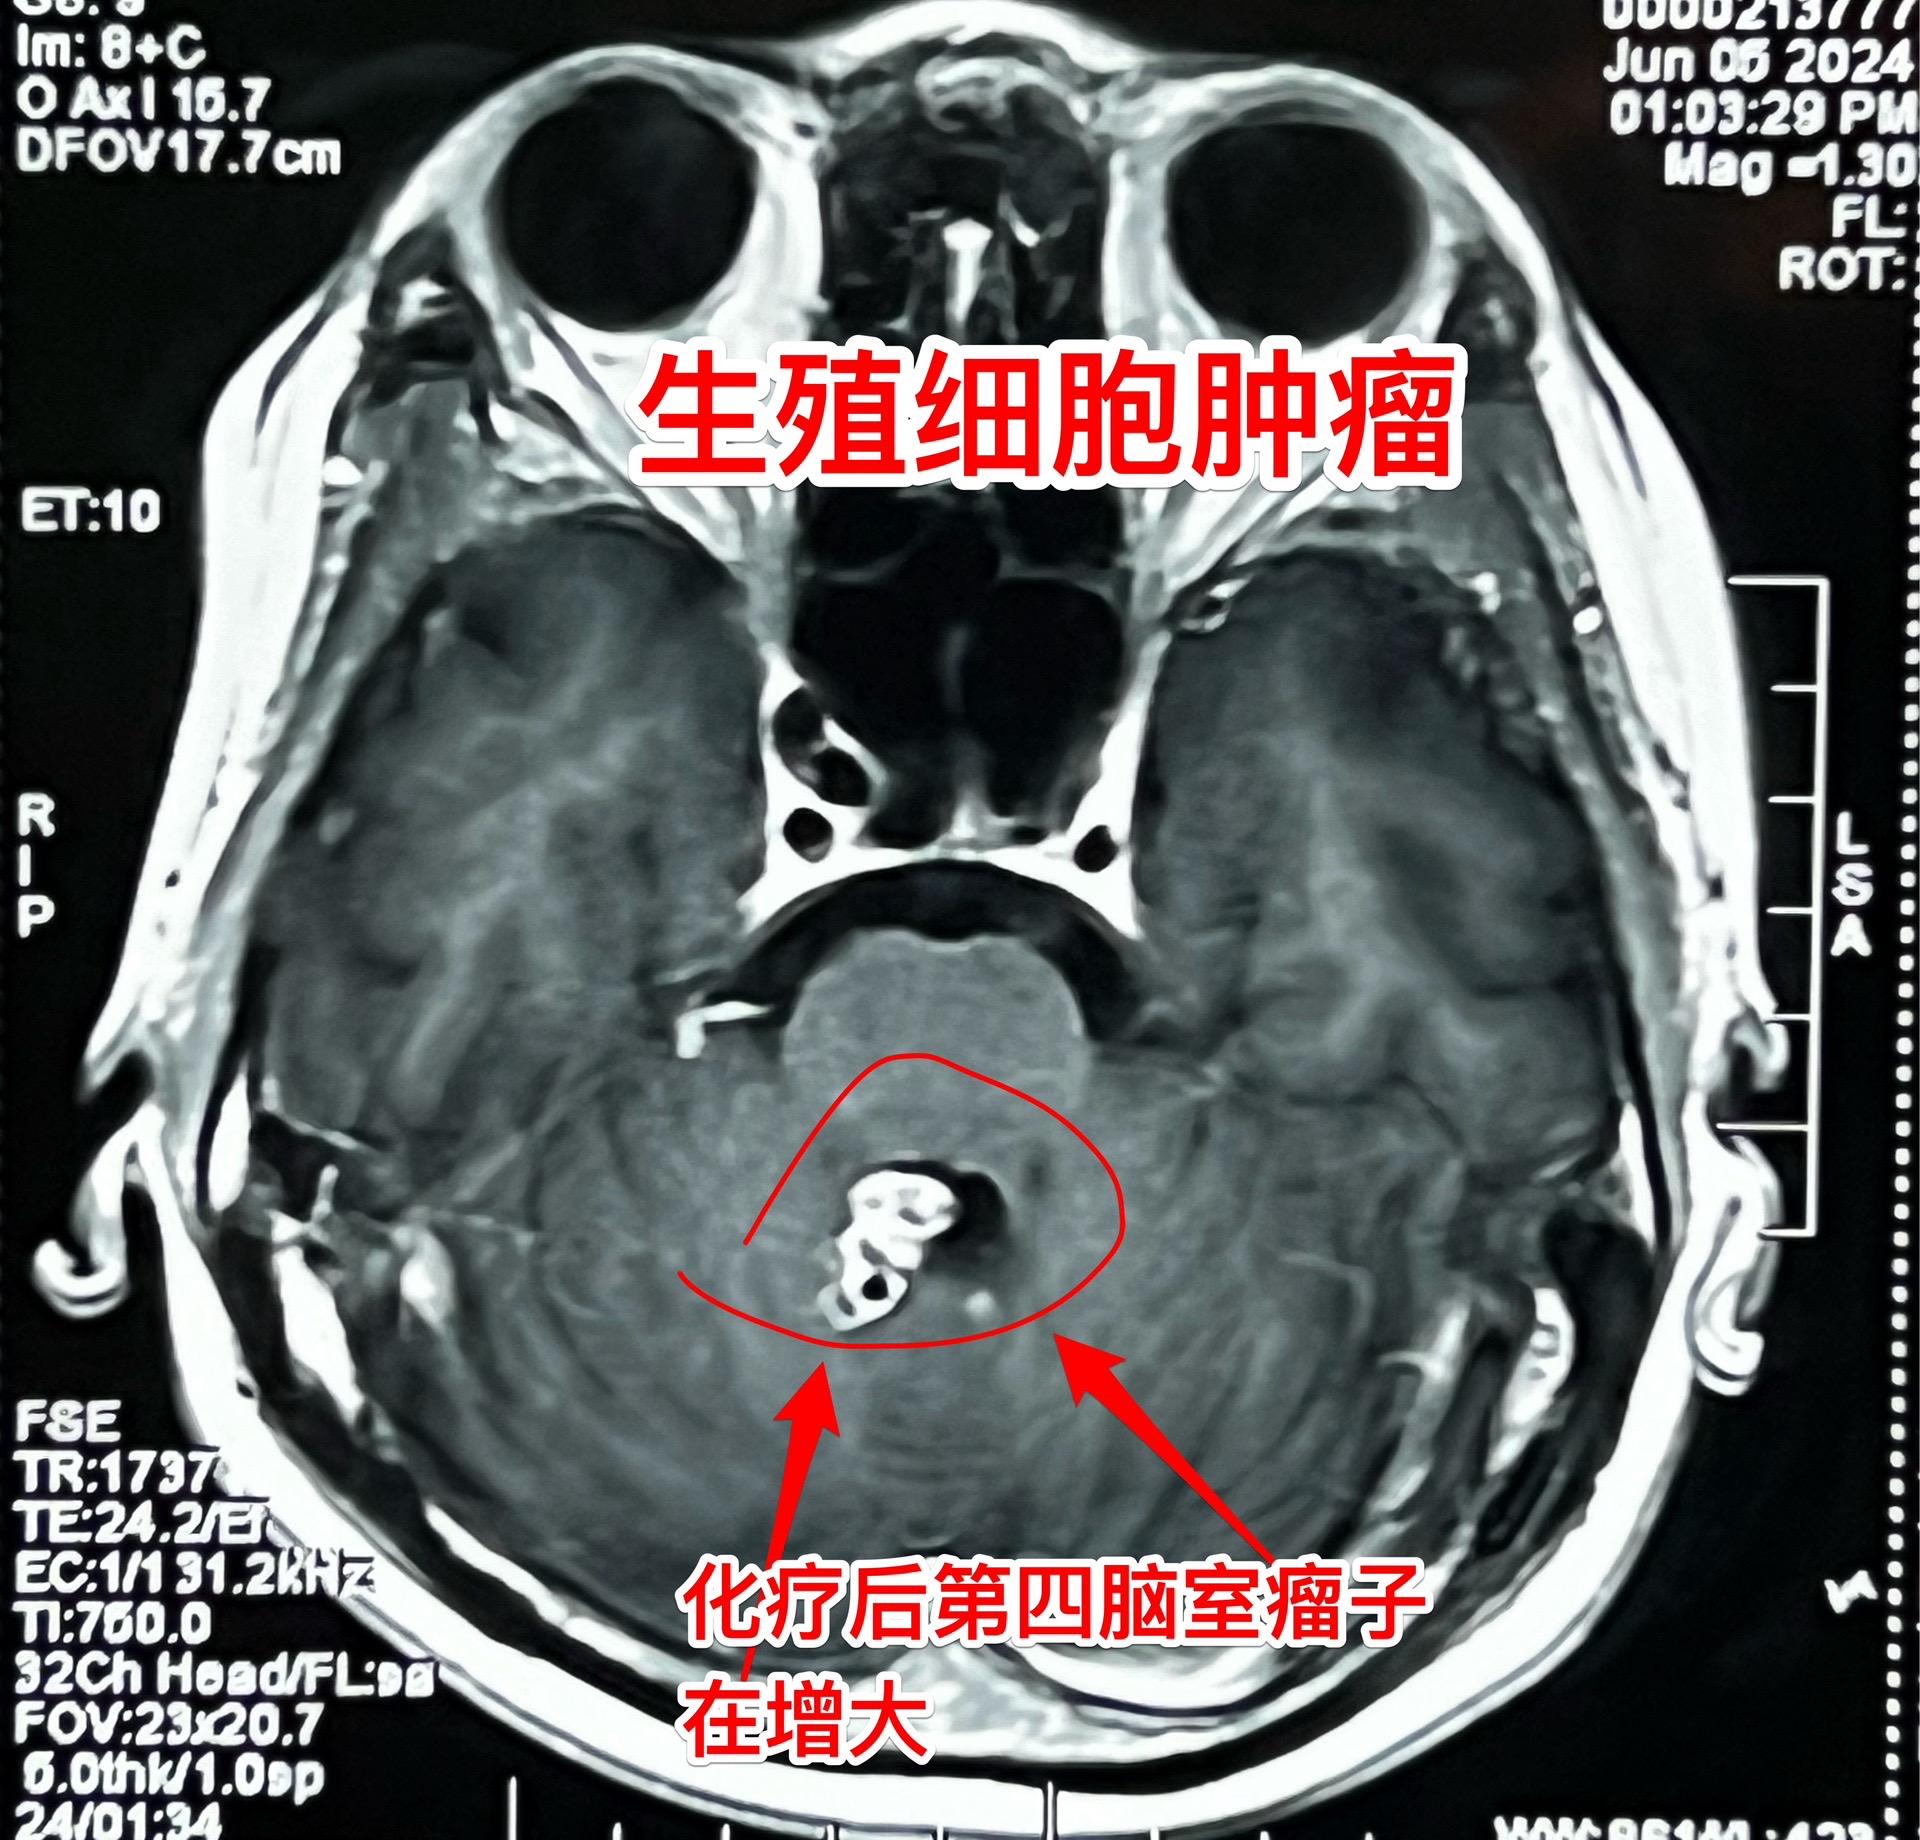

脑部生殖细胞肿瘤一般需要综合治疗。14岁广东省男孩子发现松果体区及第四脑室内多发肿瘤,怀疑是生殖细胞肿瘤。在广州市某医院作了两个疗程的化疗,松果体区的肿瘤明显变小了,但是第四脑室内的肿瘤体积却增大了! 昨天为他作了开颅手术,看见第四脑室内的肿瘤病灶一共有四个,切除了三个,另一个经过化疗后似乎坏死了!等病理报告出来后还需要综合治疗。 恶性的生殖细胞肿瘤一般需要综合治疗,该男孩子病灶有播散转移,应该是恶性肿瘤,为病人祈福🙏。